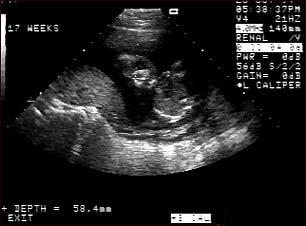

Ecografia fetala